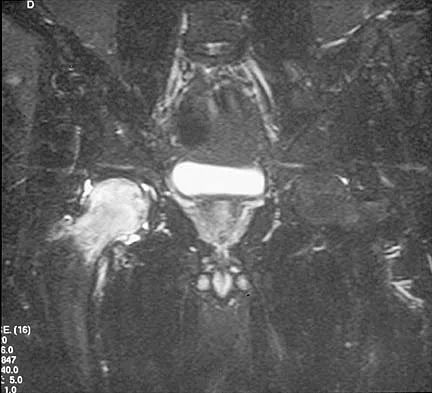

Figures 10a through 10c show the plain radiograph and MRI scans of a 41-year-old man who has right hip pain. What is the most likely diagnosis?

Explanation

Transient osteoporosis is a self-limited painful but reversible disorder. Although first described in pregnant women, it is more common in young to middle-aged men. The radiograph shows loss of mineralization in the right hip relative to the left side. There is no osseous destruction or cortical expansion typical of metastasis or giant cell tumor. The process is confined to the femoral side of the joint unlike rheumatoid arthritis, which would be centered in the joint. Osteonecrosis is better defined with sharp but irregularly shaped margins, and there is no double-line sign. The MRI scans reveal diffuse edema in the femoral head and neck that is atypical for osteonecrosis. Transient osteoporosis may recur in the same or opposite hip.